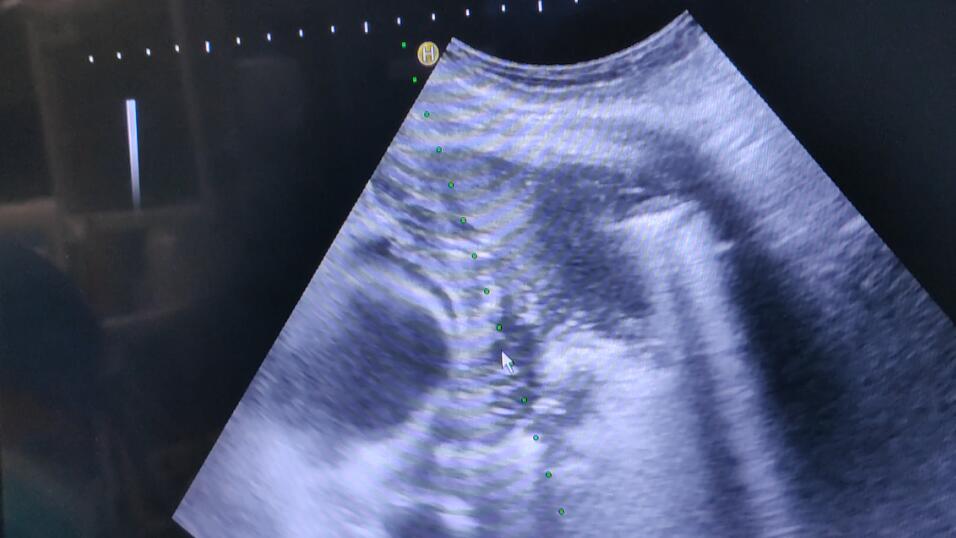

治疗前

我院专家结合既往病史及检查,由于肿瘤靠近心脏,外围肺不张,手术风险较大。在患者及家属的同意下,由牛立志院长主刀,利用全新一代康博刀机器为其实行右中肺肿瘤经皮穿刺活检+冷冻消融术。牛立志院长表示,此次治疗的重点:一是穿刺活检,可以明确肿瘤有无新的基因突变,为下一步诊疗提供方向;二是进行局部消融,控制肿瘤生长速度,为患者提高生活质量。

手术当天,在彩超实时引导下,以右中肺肿瘤为靶区,用18G活检枪穿刺到靶区,取出肿瘤组织送病理检查;再用超冷刀精准插入肿瘤组织,彩超扫描到位后100%气量冷冻15分钟两个循环,温度降至-195℃~-170℃直至见冰球覆盖靶区,复温后拔除超冷刀,包扎穿刺点,手术顺利完成。